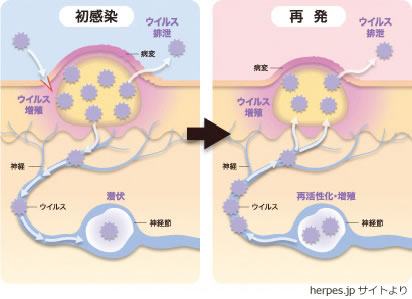

会陰 ( えいん )とは、 解剖学 において、狭義では 外陰部 と 肛門 の間、広義では左右の 大腿 と 臀部 で囲まれる 骨盤 の出口全体をさす。 恥骨結合 と左右の 坐骨結節 、 尾骨 を結ぶ菱形部となる。会陰と残尿感の解消には、 一体どのような関係性があるのでしょうか。 男性は蟻の門渡りを押すことで残尿感を解消できるのか? 排尿を終えた直後なのに「まだ膀胱内に尿が残っているような気がする、 なんだかスッキリしない」という不快感を覚える 男性の陰部のかゆみの原因として考えられる疾患とは? 男性の陰部にかゆみの症状があるとき、大まかな原因としては「性感染症」「皮膚疾患」の2つの場合が考えられます。 かゆみのある性感染症としては「性器ヘルペス・尖圭コンジローマ・梅毒」などがあり、どれも性行為により感染する可能性があります。 性器ヘルペスでは、陰部に水膨れができ

ヘルペス 山の手クリニック

デリケートゾーン 陰部 のかゆみの症状 原因 くすりと健康の情報局

丸善クリニック 性器ヘルペス ウイルス性